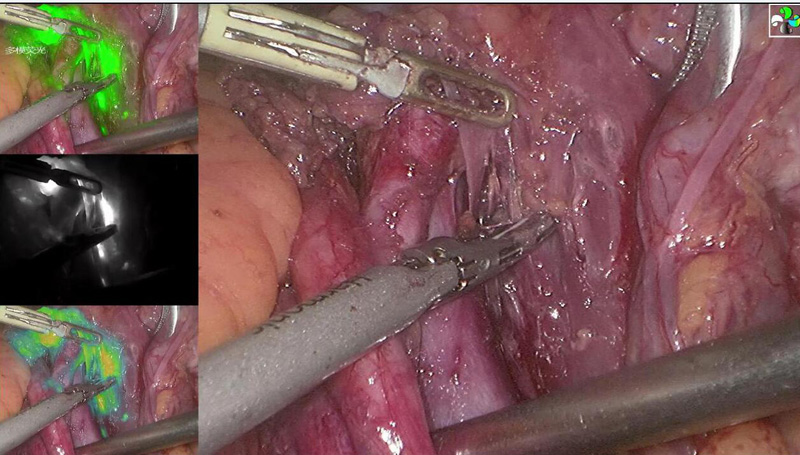

2018年11月21日,安阳市人民医院妇科薛惠英主任、刘现红副主任医师及张利姣医师,在麻醉科安波主任医师、护士雷欢欢、李敏的协助下开展了我市首例荧光内镜系统引导下妇科肿瘤前哨淋巴结精准定位及淋巴示踪手术,为早期妇科恶性肿瘤患者的治疗提供了更加精准的医疗服务。

(欧谱曼迪荧光)腹腔镜下前哨淋巴结显影,为妇科恶性肿瘤的精准治疗和个体化治疗提供一把利器,这标志着安阳市人民医院妇科医疗技术水平又跃上新台阶。

荧光标记淋巴,术中实现精准光学导航。

精准切除显影淋巴结

彩色荧光模式